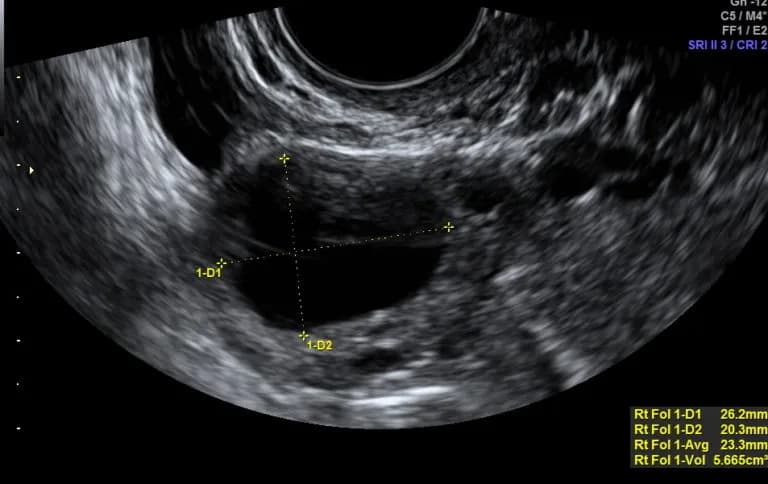

Następnie ciałko krwotoczne przekształca się w ciałko żółte, które jest kluczowe w cyklu miesiączkowym. Na USG ciałko żółte może mieć różne cechy wizualne, w tym przestrzeń płynową o wielkości od 1 do 2 cm lub torbiel o średnicy 3–4 cm. Jest to struktura bardzo unaczyniona, co można zobaczyć za pomocą kolorowego Dopplera, który ukazuje niski opór przepływu krwi wokół ciałka żółtego, tworząc tzw. „pierścień ognia”.

Ciałko żółte odgrywa kluczową rolę w cyklu miesiączkowym, produkując hormony, które wspierają potencjalną ciążę. Na USG ciałko żółte może mieć różne cechy wizualne, w tym grubą, ząbkowaną ścianę lub torbielowate struktury. Jego obecność jest szczególnie istotna w przypadku zapłodnienia, gdyż ciałko żółte przekształca się w ciałko ciążowe, które wspiera rozwijający się zarodek. Ciałko żółte jest najlepiej widoczne na USG około 7–9 dni po owulacji.